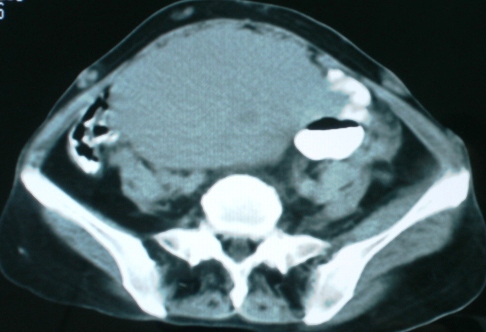

以下是引用zsl6918在2008-11-4 19:14:00的发言:[br]多发转移性改变,子宫改变不除外为原发灶